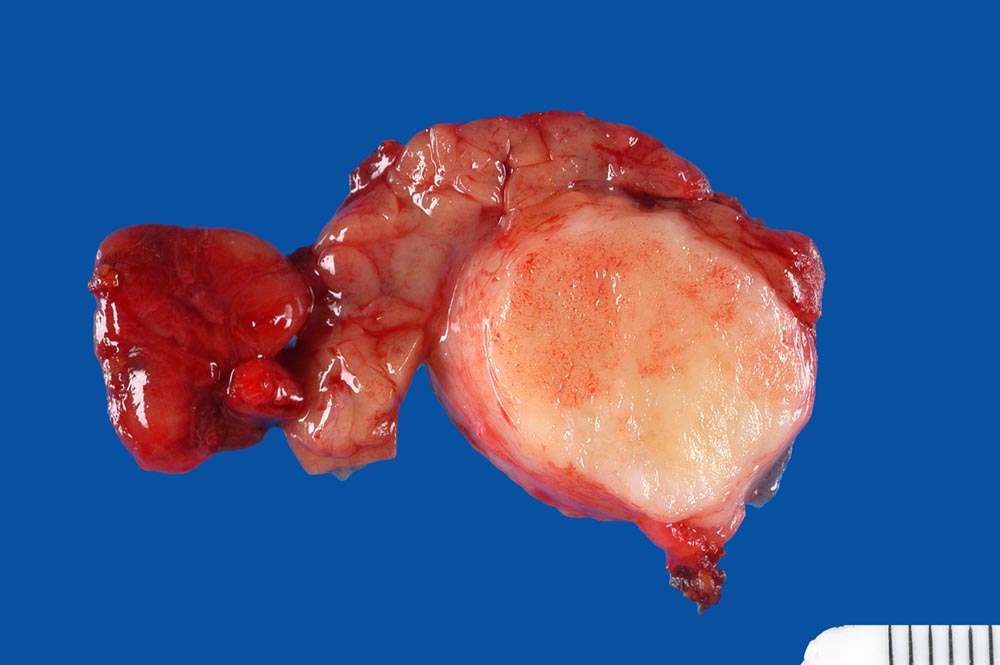

Makroskopie:

Makroskopisch sind pleomorphe Adenome scharf begrenzt. In den grossen Speicheldrüsen sind die meist solitär wachsenden Knoten von einer Kapsel umgeben, nicht aber in den kleinen Speicheldrüsen. Rezidivtumoren bilden oftmals multiple Knoten.

Makroskopie

Befund

Pathologischer Befund